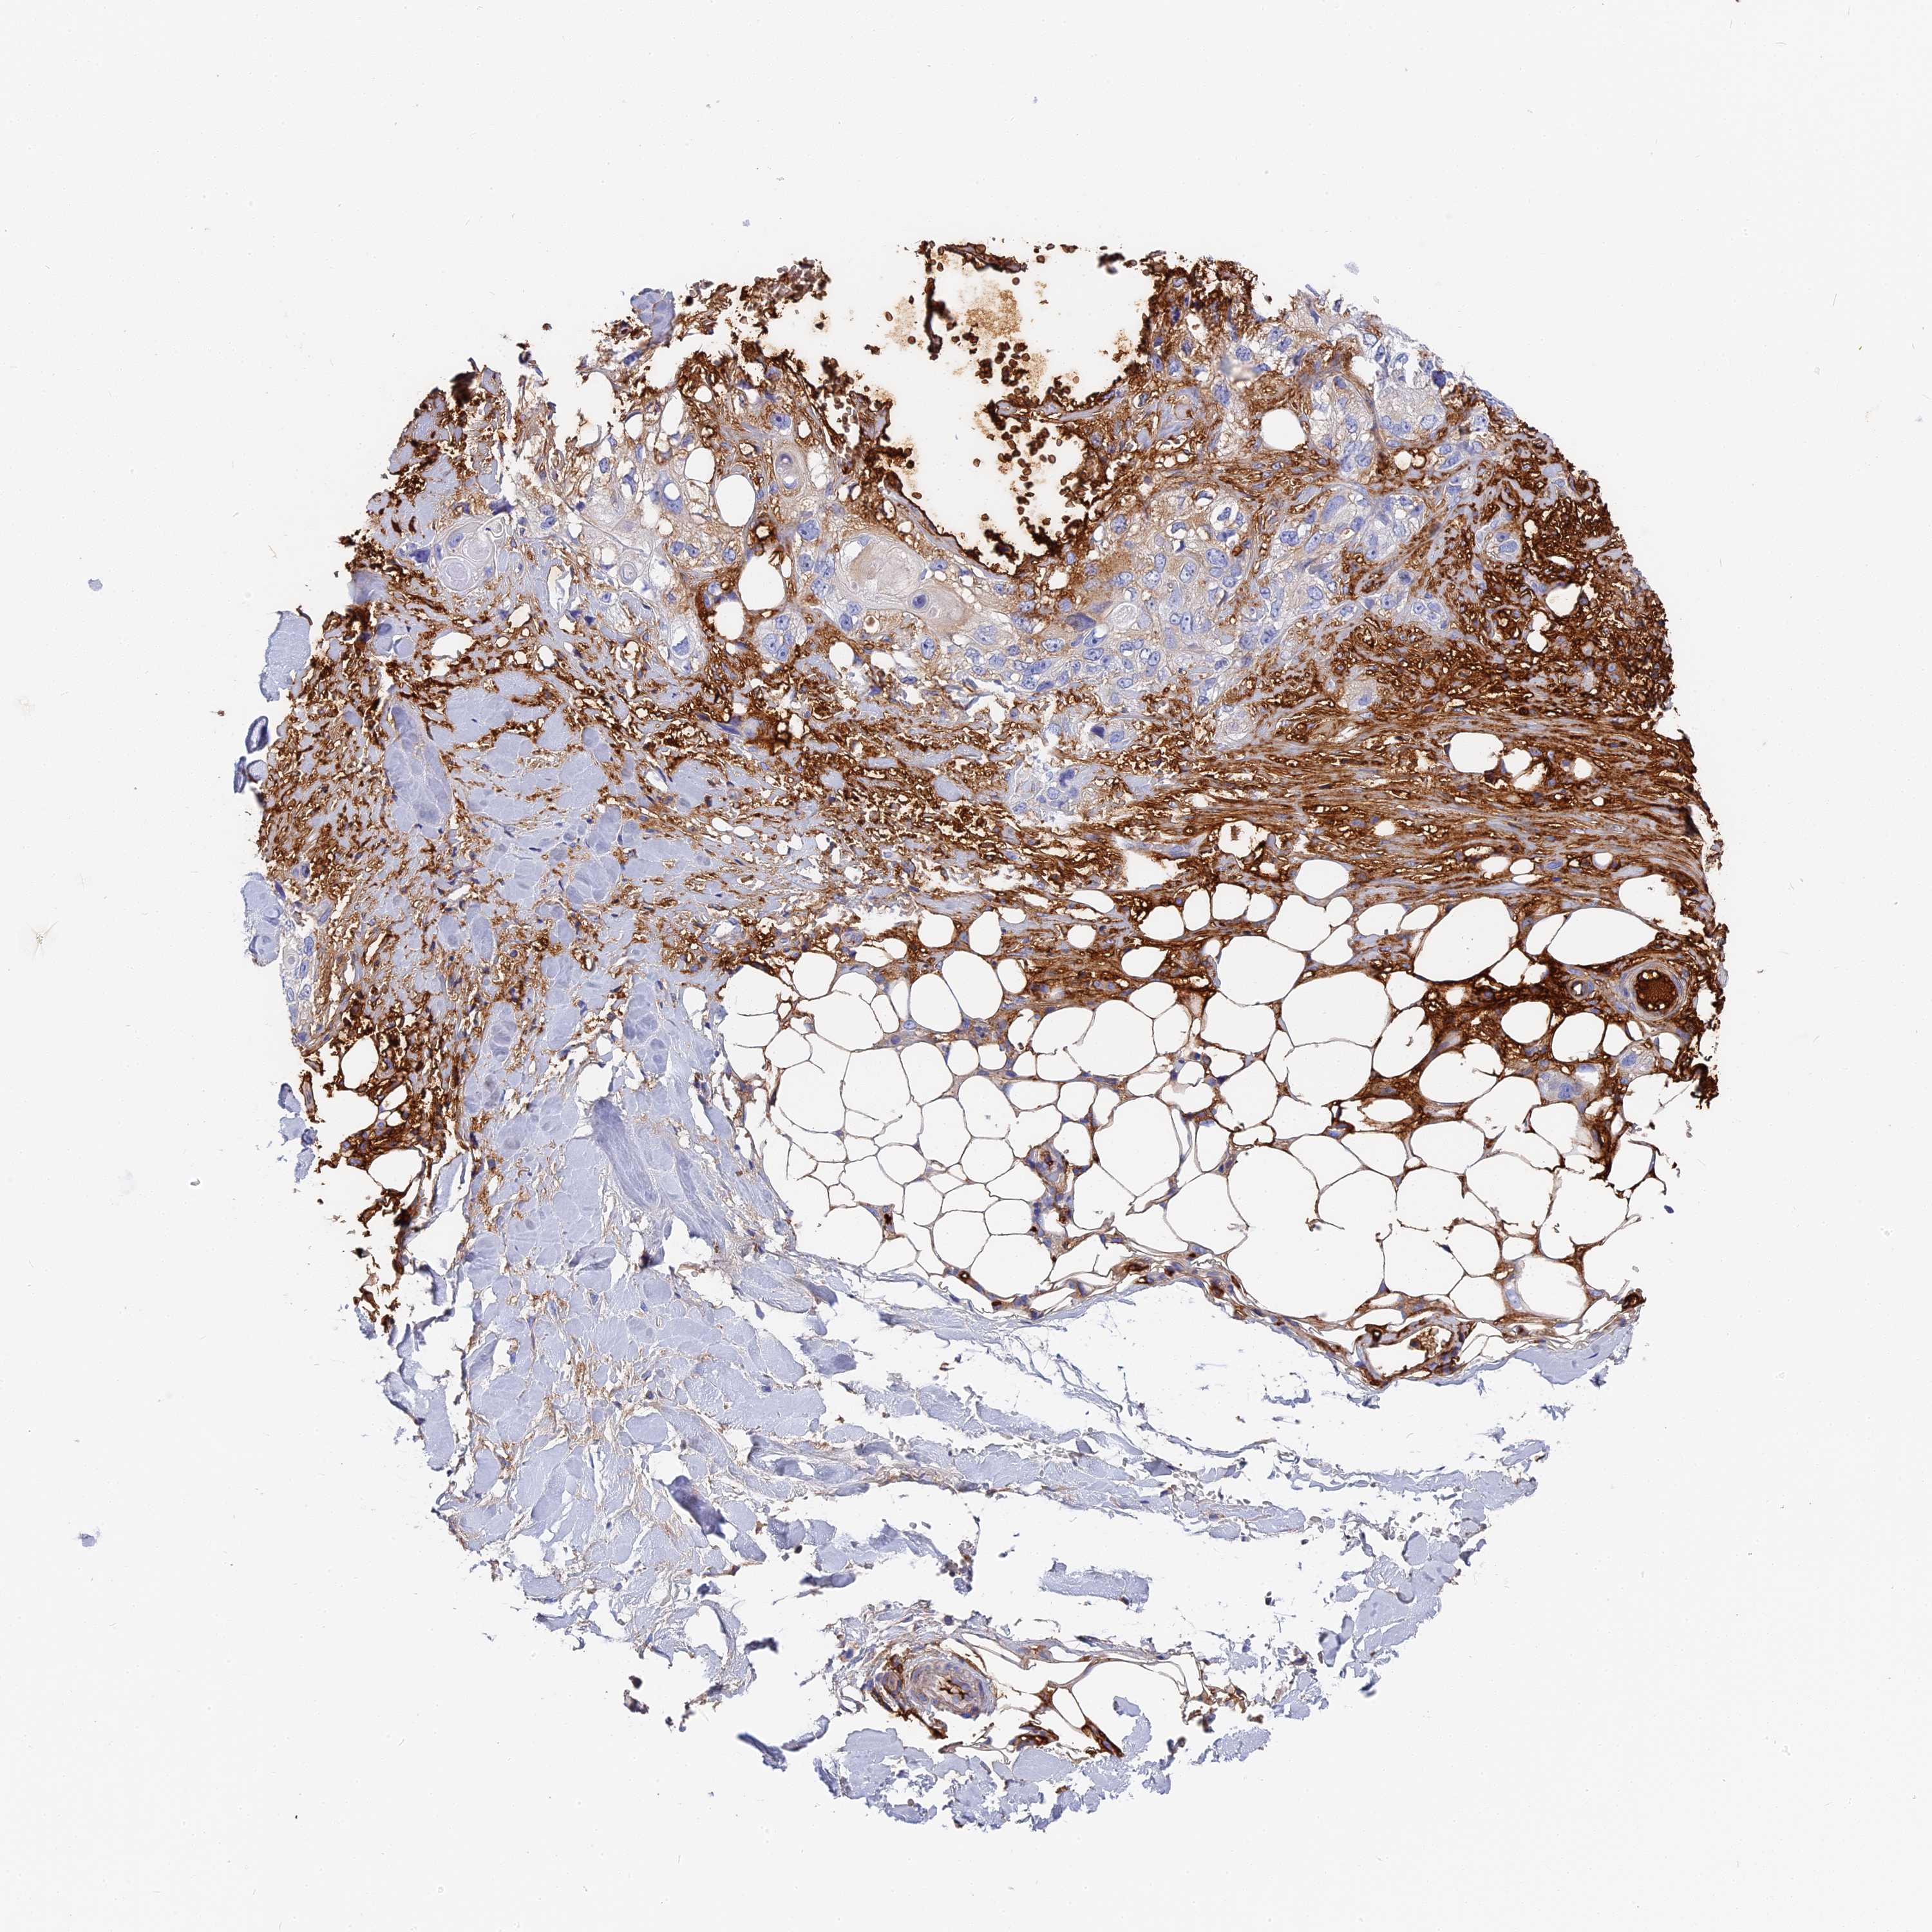

SKIN CANCER - Protein expressioni

A mouse-over function shows sample information and annotation data. Click on an image to view it in a full screen mode. Samples can be filtered based on level of antibody staining by selecting one or several of the following categories: high, medium, low and not detected. The assay and annotation is described here.

Antibody stainingi

Antibody staining in the annotated cell types in the current human tissue is reported as not detected, low, medium, or high, based on conventional immunohistochemistry profiling in selected tissues. This score is based on the combination of the staining intensity and fraction of stained cells.

Each image is clickable and will lead to virtual microscopy that enables deeper exploration of all samples and also displays staining intensity scores, fraction scores and subcellular localization as well as patient and tissue information for each sample.

Antibody HPA041639

Antibody HPA042049

Squamous cell carcinoma, metastatic, NOS